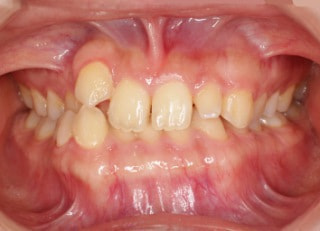

治療法:フルパッシブブラケット:T21

治療後(2年11ヶ月後)